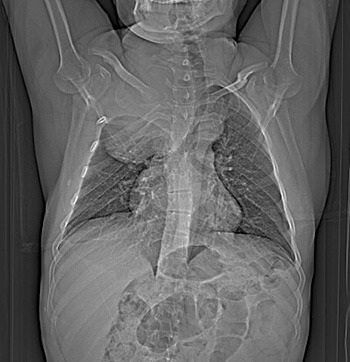

УЗИ и рентгенография

Такие методы обследования назначают, чтобы проследить изменения, выявить метастазы в пищеводе, бронхах и легких.